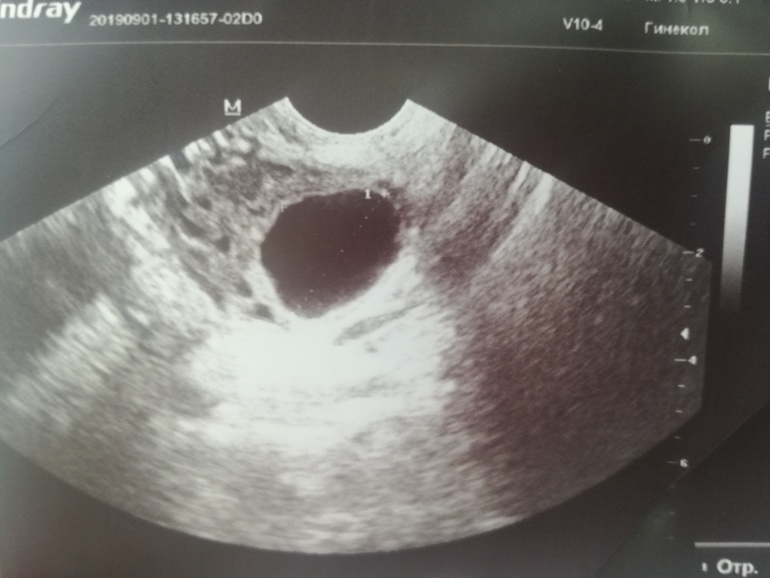

На 18 ДЦ пришла промониторить,узистка смотрела -смотрела и говорит не знаю или фолликулярная или киста желтого тела размер 26мм,Э 10мм

сходила..в итоге лопнул!!и сказали киста желтого тела,но...она огромная,64мм..врач написала киста желтого тела с кровоизлиянием(((не одно так другое

У меня в прошлом цикле была такая киста на узи, по фотке похожа) в итоге сдулась сама, в этом цикле от неё не осталось и следа, и была нормальная овуляция)